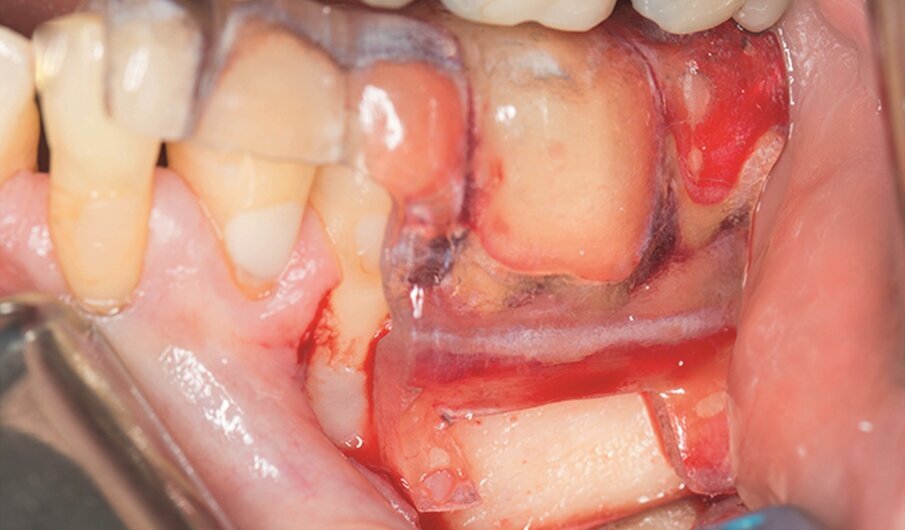

Under local anaesthesia, a full-thickness mucoperiosteal‑ap was reflected, providing visualisation of the buccal bone (Fig. 2g), and the printed template was used to mark the cortical window (Fig. 2h), which was cut with a Piezotome CUBE LED handpiece, and the separated instrument was exposed (Fig. 2i) and removed (Fig. 2j). After apicectomy, retro-preparation was done using ultra sonic tips (ACTEON) and sealed with TotalFill BC RRM Fast Set Putty (FKG) (Fig. 2k). The ‑ap was sutured using 5/0 prolene suture material (Fig. 2l). The sutures were removed 72 hours postoperatively. After two years the patient came to our office for a follow-up radiograph, the tooth was asymptomatic and in function (Fig. 2m).

Fig. 2h: The template was adjusted and the limits of the cortical window were marked in the bone.

Fig. 2i: Separated instrument out of the root near the apical area of tooth #15.